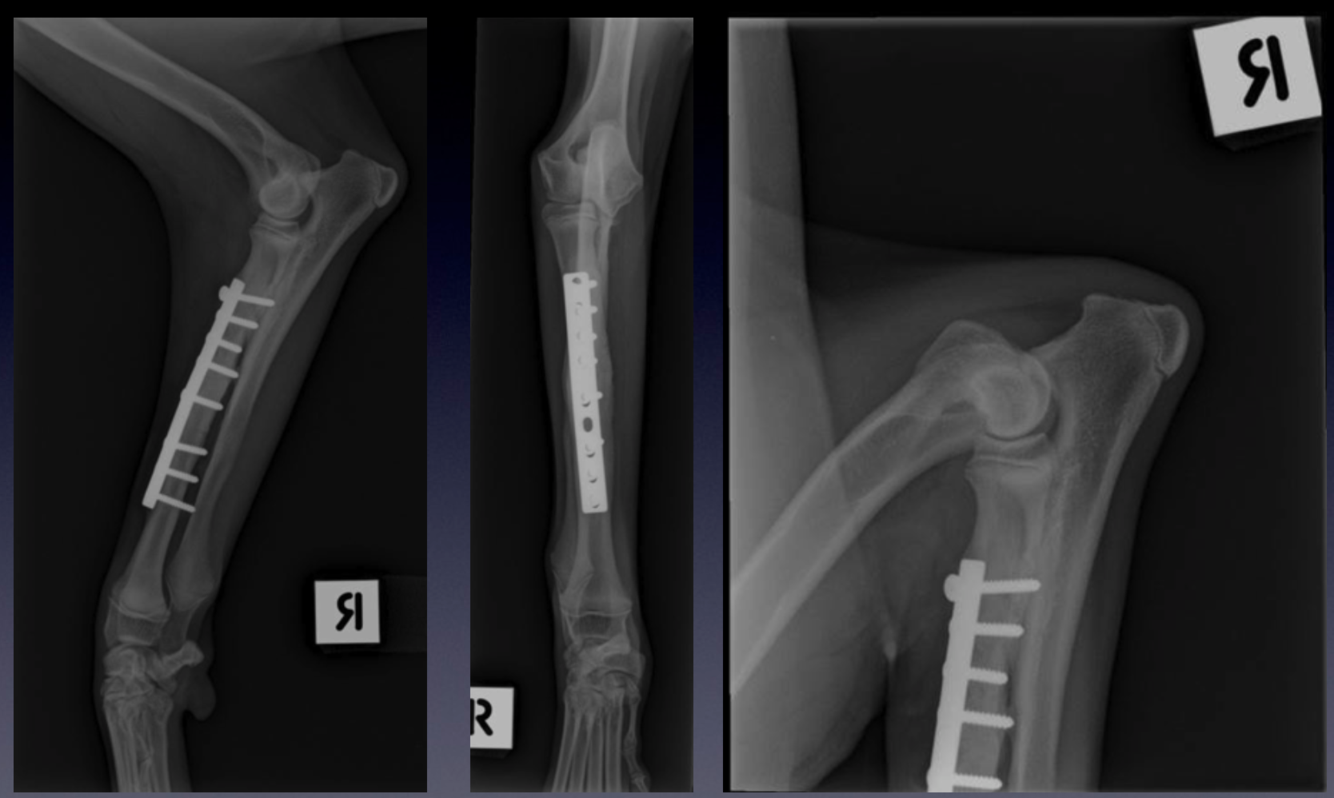

Case 5: Patient 239711

VIEW??

Please refer to the normal elbow for comparison.

Review the normal anatomy of the elbow joint. In this patient, note the conical shape of the distal ulna physis.

Note the growth plate of the tuber olecrani - this separate centre of ossification is called an apophysis. What

The surgical plate on the cranial aspect of the radius, which stabilised a diaphyseal fracture, now healed - a

fracture line is no longer visible.

Note that the most proximal screw crosses to the ulna, fixing the radius to the ulna. Note that this screw has

partially ‘backed out’, with angulation of this screw and the screw head no longer flush with the plate surface.

The elbow joint is incongruent, with a large ‘step’ between the radial head and medial coronoid process of

the ulna, and subluxation of the humeral condyle from the ulna trochlea notch.

The distal ulna physis is located slightly more proximally than the distal radial physis - normally they are

located at a similar level. The distal ulna physis is more indistinct, as it is beginning to radiographically close.

This is an example of acquired elbow incongruity. The ulna is shortened relative to what it should be: this is

probably due to premature closure of the distal ulna physis, probably due to the same traumatic event that

caused the fracture to the radius.

Mediolateral and craniocaudal projections of the antebrachium, and flexed mediolateral projection of the

elbow of a skeletally mature dog.